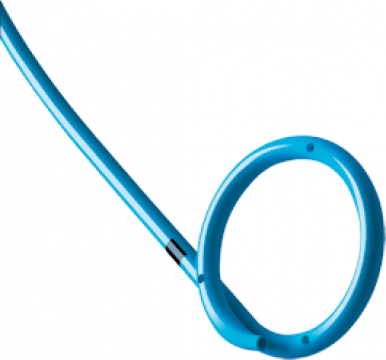

Sonda Cook, sau sondă dublu J (JJ), este un dispozitiv medical folosit în urologie pentru a menține deschiderea ureterului și a permite drenajul eficient al urinei din rinichi către vezica urinară. Aceasta este flexibilă, are o formă curbată la ambele capete, asemănătoare literei „J”, și este fabricată din materiale biocompatibile, precum siliconul sau poliuretanul, pentru a asigura confortul și siguranța pacientului. Sonda este utilizată în diverse situații, inclusiv obstrucții urinare sau după intervenții chirurgicale.

Sonda Cook este concepută să mențină deschis ureterul, tubul care transportă urina de la rinichi la vezica urinară, prevenind obstrucțiile și asigurând drenajul constant al urinei. Cele două capete curbate în formă de „J” se fixează unul în rinichi (calicele renale) și celălalt în vezica urinară, pentru a preveni migrarea sau deplasarea sondei.

- Fixarea sondei: Cele două bucle în formă de „J” se formează automat la ambele capete pentru a fixa sonda în poziție și a preveni deplasarea.